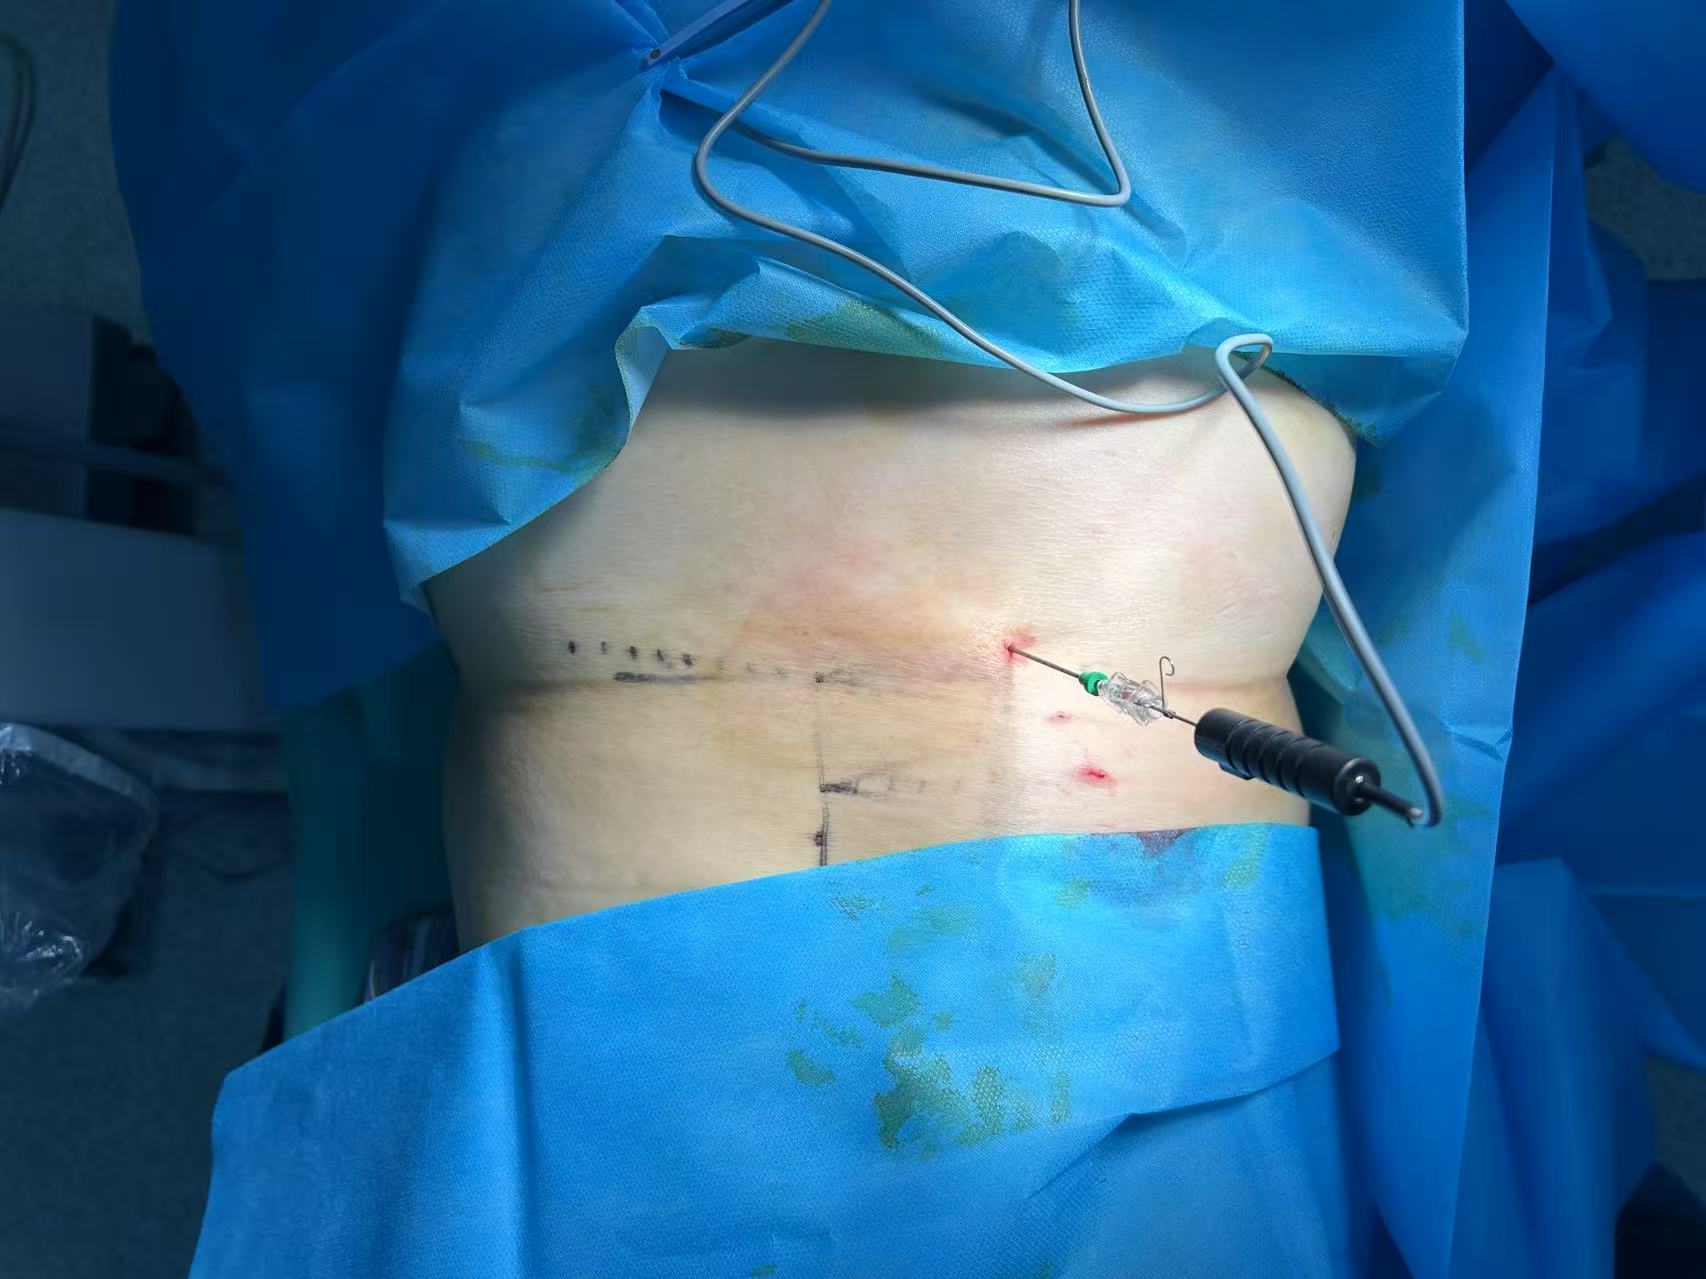

体位与麻醉

:患者通常采取俯卧位,医生会在腰部手术区域进行消毒、铺无菌巾,随后注射局部麻醉药(一般为利多卡因),麻醉过程中患者可能会感到轻微胀痛,但无明显疼痛。

穿刺定位

:医生通过 C 型臂 X 光机或 CT 引导,将射频穿刺针精准刺入突出的髓核内部。这一步是手术的关键,影像引导可确保穿刺针不损伤神经和血管,患者此时可能会感到腰部有轻微酸胀感,但需保持身体不动,配合医生操作。